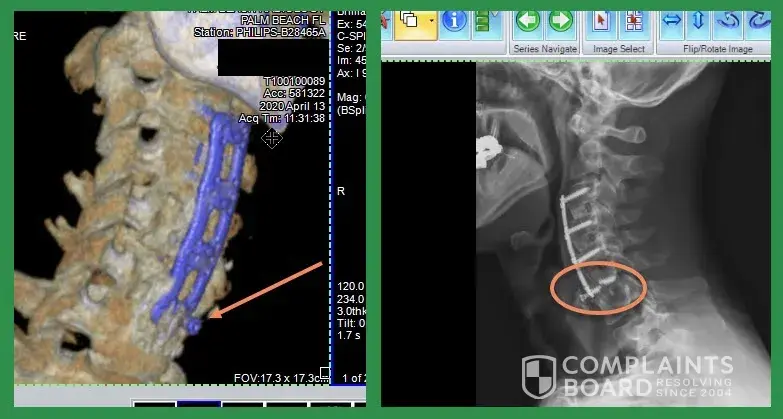

Read full complaintNexxt Spine - Spinal fusion surgery hardware

I had a triple spinal cervical fusion surgery (C3-C7) in Arizona in 2017. The surgeon was Dr. Paul Gause from the Spine Institute of Arizona. The surgery was at Thompson Peak Medical Center in Scottsdale, AZ. According to the Implant Summary Sheet, the hardware used was manufactured by two companies: Nexxt Spine and SeaSpine. Immediately following surgery...